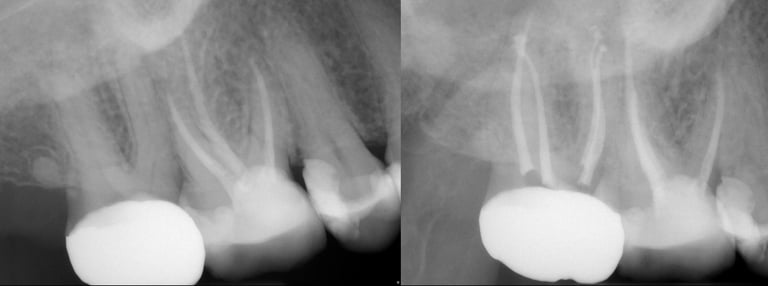

Gallery 2: Retreatment Cases

Retreatment Root Canal Cases with preoperative and postoperative radiographs.

#10 ReTx (original RCT poorly done)

#14 ReTx (original RCT had missed 4th canal)